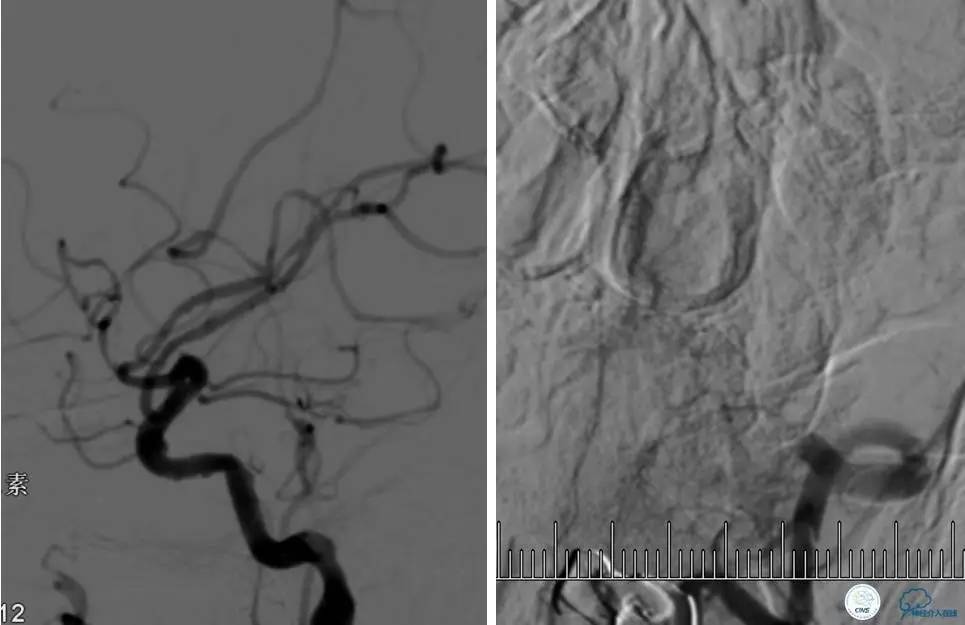

患者:53岁男性,反复脑梗死3个月。

▼给予球囊扩张成形,闭塞段较长,决定药物治疗视察,二期再给予支架治疗。

▼药物治疗1个月,再次发作。再次来我院支架治疗。

▼支架术后,效果好。

因此,某些患者分期治疗也具有合理性。